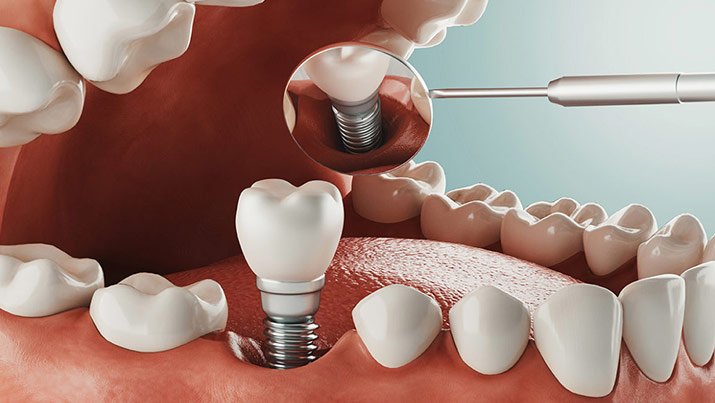

ایمپلنت فوری یک روش پیشرفته در زمینه ایمپلنت دندان است که به بیماران این امکان را میدهد تا در یک نوبت و در عین حالی که دندانهای طبیعیشان را از دست دادهاند، ایمپلنتهای جدید را دریافت کنند. این روش با استفاده از تکنولوژیهای پیشرفته و برنامهریزی دقیق، فرآیند کاشت ایمپلنت را تا حد ممکن سریع و کارآمد میکند. ایمپلنت فوری به بیماران این امکان را میدهد که بدون انتظار طولانی و با یک جلسه کاشت، به تجربه لبخند زیبا و کارایی بینظیر ایمپلنت دست یابند. این روش مناسبی برای افرادی است که نیاز به جایگزینی سریع و موثر دندانهای خود دارند و میخواهند به سرعت به عملکرد طبیعی دهان خود باز گردند.

ایمپلنت ارزان فوری به عنوان یک راه حل پیشرفته در زمینه دندانپزشکی، مزایای فراوانی برای بیماران ارائه میدهد. یکی از مهمترین مزایای این روش، سرعت و سهولت در انجام فرآیند جایگزینی دندان است. با این روش، بیماران توانایی بهبود فوری از نظر ظاهری و کارکردی دهان خود را به دست میآورند، بدون اینکه نیاز به انتظار طولانی برای جلسات درمانی داشته باشند. علاوه بر این، ایمپلنت فوری بهبود قابل توجهی در اعتماد به نفس بیماران ایجاد میکند زیرا آنها بلافاصله پس از اجرای روش، از لبخند زیبا و دندانهای ثابت بهرهمند میشوند. این روش همچنین از نیاز به استفاده از دندانهای مصنوعی موقت جلوگیری میکند و بیماران را از دچاریها و نگرانیهای مرتبط با آنها رها میکند. در نهایت، ایمپلنت فوری به بیماران این امکان را میدهد که به سرعت به زندگی با دندانهای ثابت و طبیعی خود باز گردند.